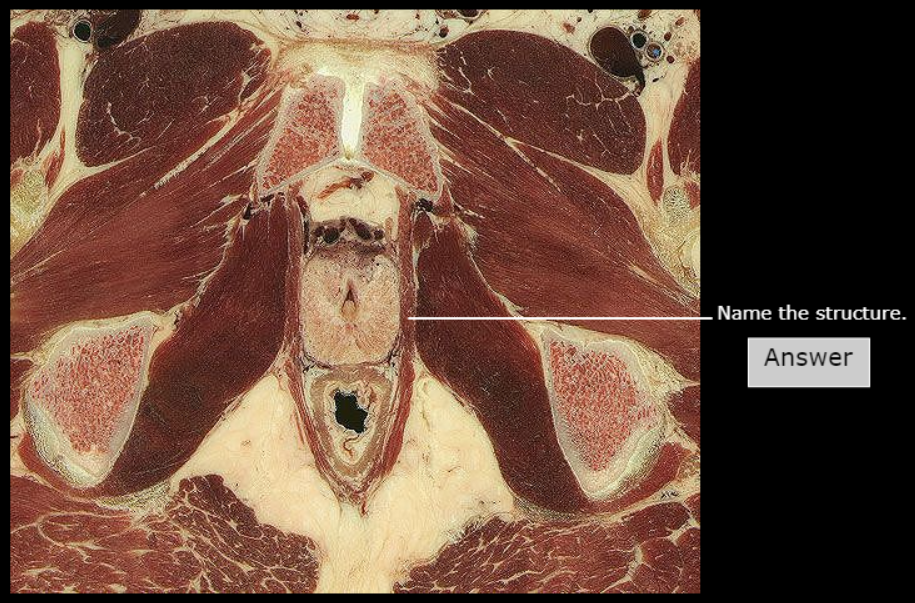

Internal Urethral Orifice